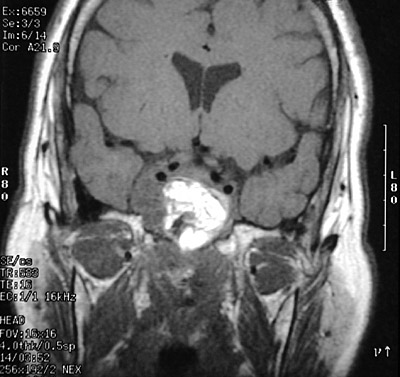

The region of the clivus (sella turcica) has a large destructive mass seen with T1 weighted MRI scan above and with gadolinium contrast in coronal and axial views below. This is a chordoma.